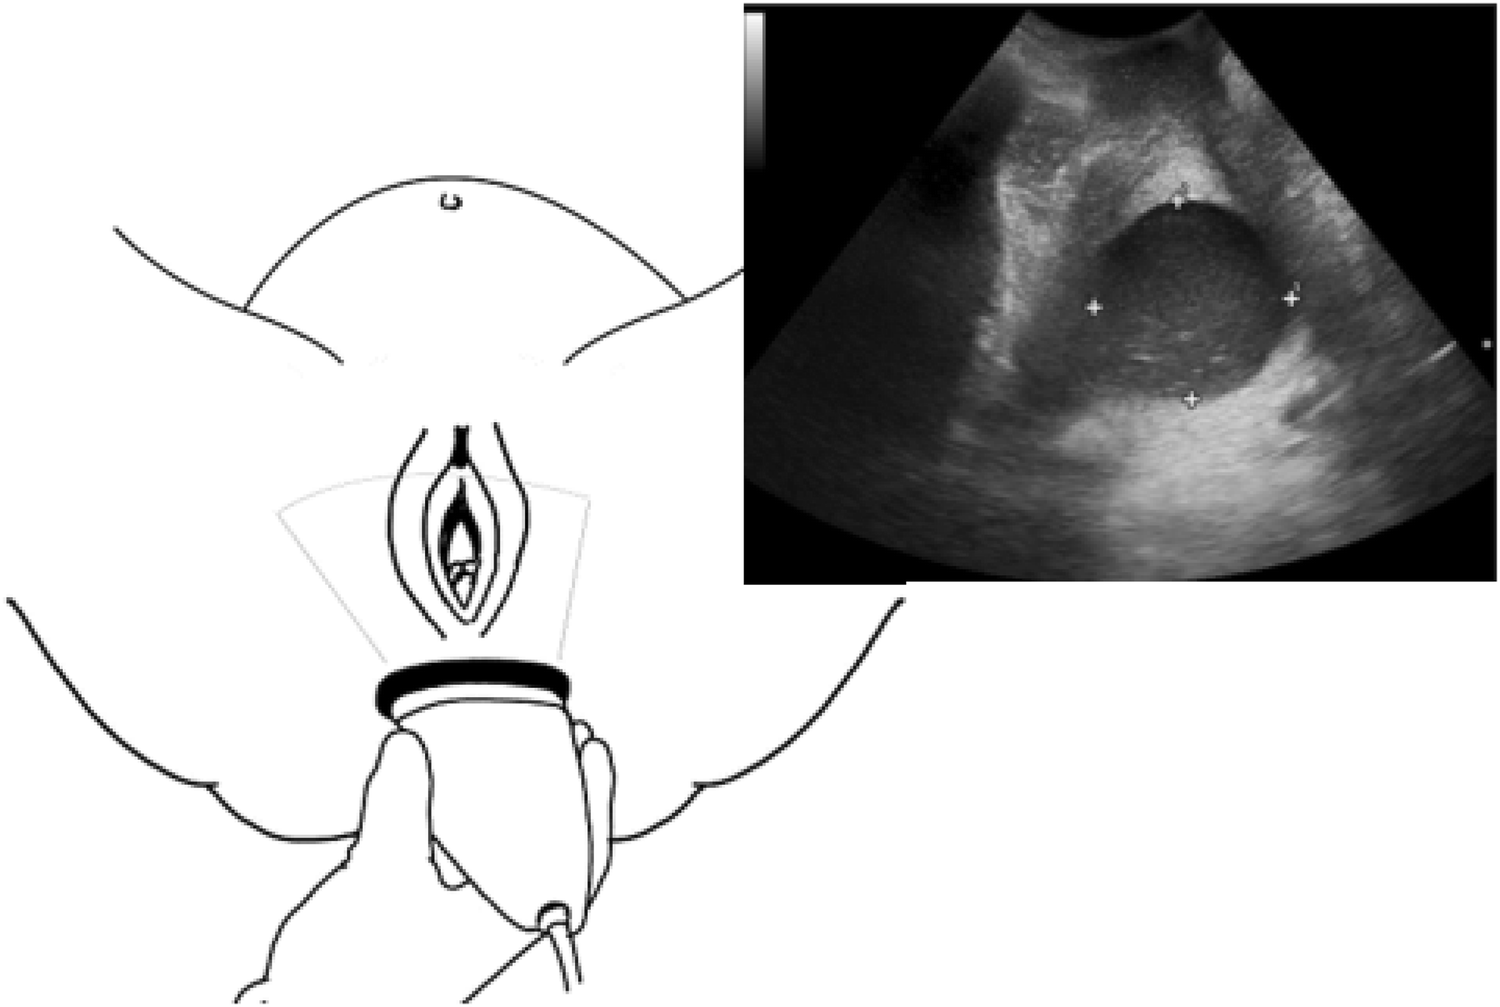

From link.springer.com

Intrapartum ultrasound assessment of cervical dilatation and its value in detecting active labor What Cervical Dilation Is Active Labor Once you're in active labor — when. The cervix must be 100% effaced and 10 cm dilated before a vaginal delivery. Labor is defined as regular and painful uterine contractions that cause progressive dilation and effacement of the. On pelvic exam, the resident notes that the patient's cervix is 2 cm dilated and 20% effaced, and she is having regular. What Cervical Dilation Is Active Labor.